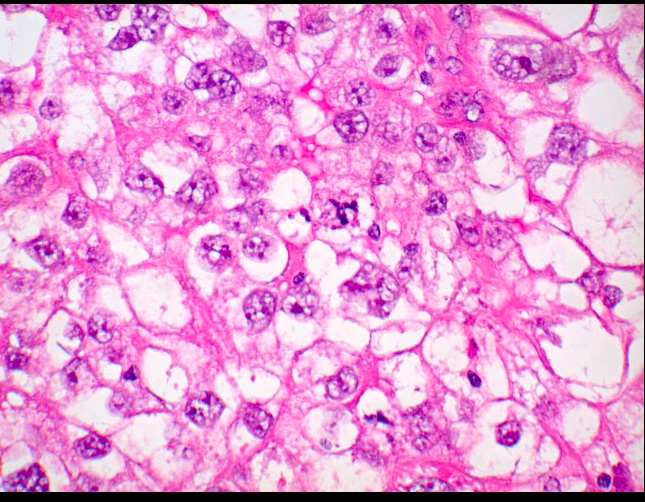

Clear Cell Adenocarcinoma

_Clear Cell Adenocarcinoma of the vagina is a rare, malignant tumor of glands with clear cytoplasm that is a complication associated with diethylstilbestrol-associated vaginal adenosis. It is commonly associated with exposure to DES in utero (Estrogen crosses placenta, distrupting development of squamous epithelium)

_When viewed microscopically, the tissue demonstrates cells with hyperchromatic nuclei (also known as "Hobnail" nuclei) protruding into the gland lumen.

Clear cell adnocarcinoma:

Hobnail nuclei: